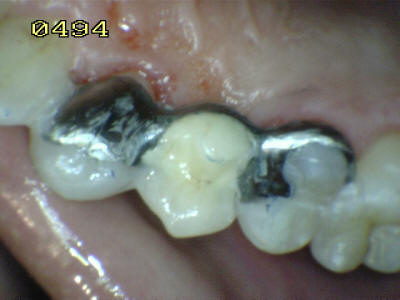

El material oscuro es una amalgama cubierta por el diseño del puuente; observe los restos de cemento adherido al esmalte dental. Caries  de esmalte y dentina en el otro pilar (flechas rojas)

Aspecto vestibular del r3emanente dentario Eliminada la caries, micro-arenado con óxido de aluminio y grabado total con acido ortofosforico (Flechas blancas)

Procedimiento de cementado, se debe tener cuidado de eliminar los excesos de cemento (flechas blancas) antes de su endurecimiento; dado que el espesor de cemento puede ser importante por la desadaptación por caries.